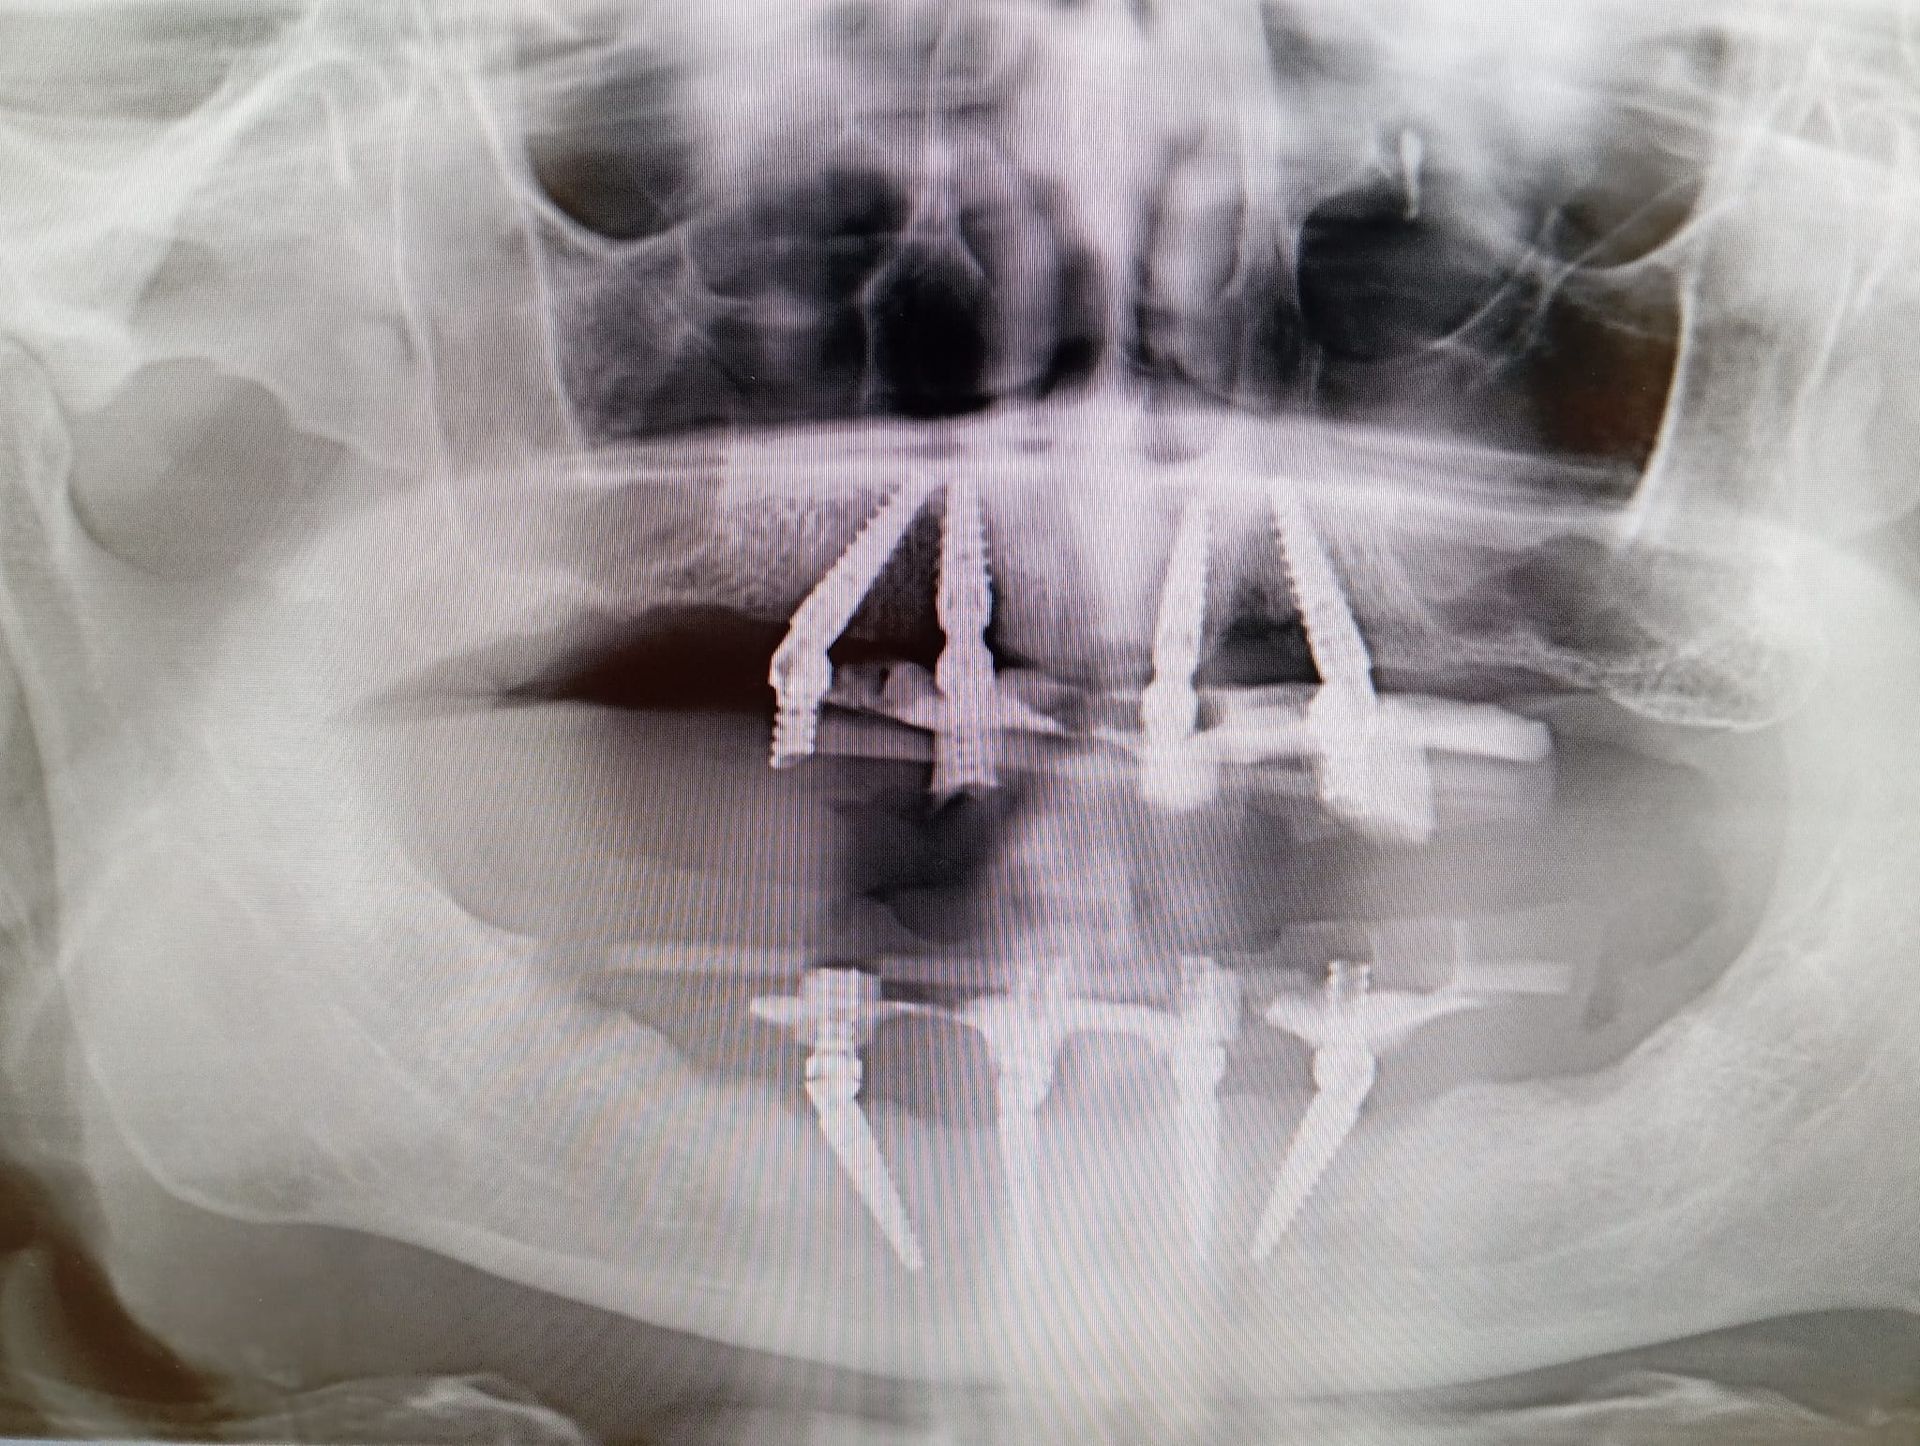

L’implantologia dentale è una branca dell’odontoiatria che ha l’obiettivo di ripristinare i denti mancanti mediante l’inserimento di radici artificiali in titanio (impianti dentali).

Le tecniche di implantologia dentaria permettono una riabilitazione permanente della masticazione

ed evitano i fastidi legati all’utilizzo di protesi mobili, assicurando un risultato estetico